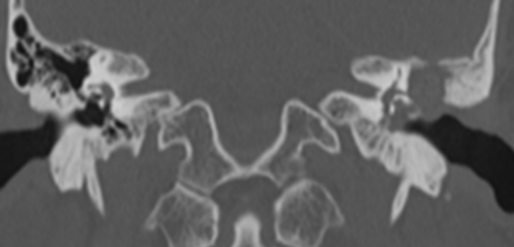

患者可以流脓或不流脓,脓一般有特殊的臭味。可以有较重的传导性耳聋或混合性耳聋。查体可见鼓膜松弛部、紧张部后上方穿孔,或边缘性穿孔,穿孔内可见胆脂瘤皮或肉芽。影像学:CT示上鼓室、鼓窦或乳突骨质破坏,边缘整齐。